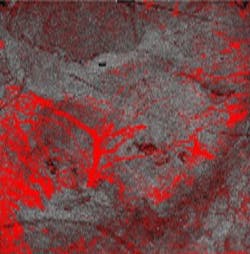

A dynamic OCT image of early-stage melanoma taken with the VivoSight scanner is shown; the red dots and lines are small blood vessels. (Photo credit: PRNewsfoto/Michelson Diagnostics)

"Cancers grow their own blood vessel network to supply oxygen and nutrients," explains Nathalie de Carvalho of the University of Modena and Reggio Emilia and the study's lead author. "We analyzed the shapes of the vessels in the OCT images of melanomas and correlated the frequency of different shapes with the Breslow depths (the thickness of the tumors, measured from biopsy samples). We found that certain vessel shapes appeared much more frequently in thicker tumors. The vessels grown by the tumor seem to grow more chaotically and become more malformed as the cancer progresses."